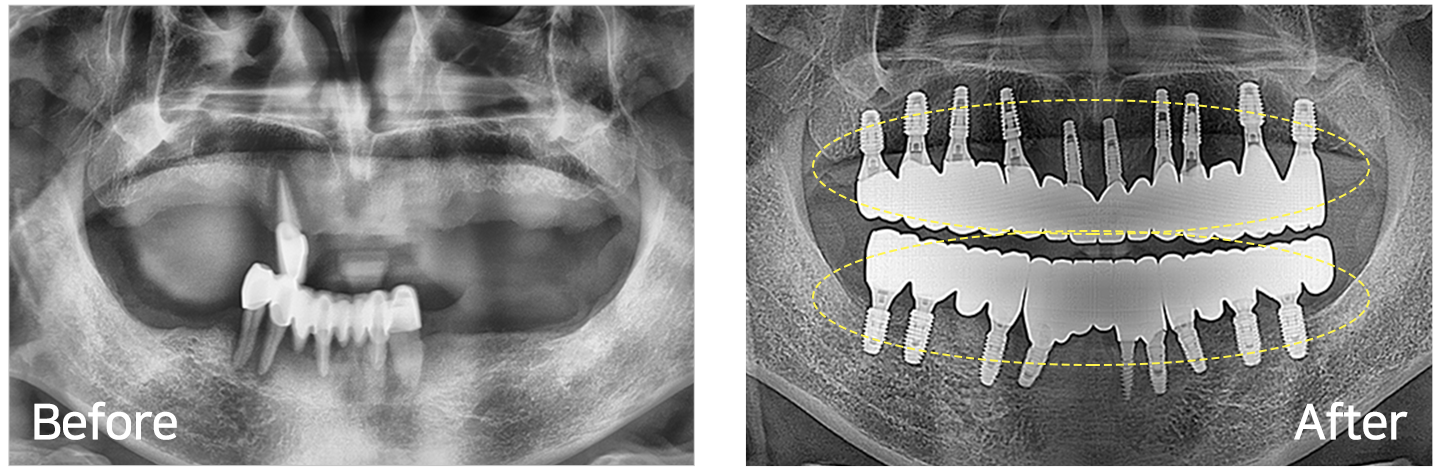

임플란트 시술 사례

IMPLANT TREATMENT CASES

※ 전신질환 및 관리 능력에 따라 임플란트 주위염 등의 부작용이 있을 수 있습니다.